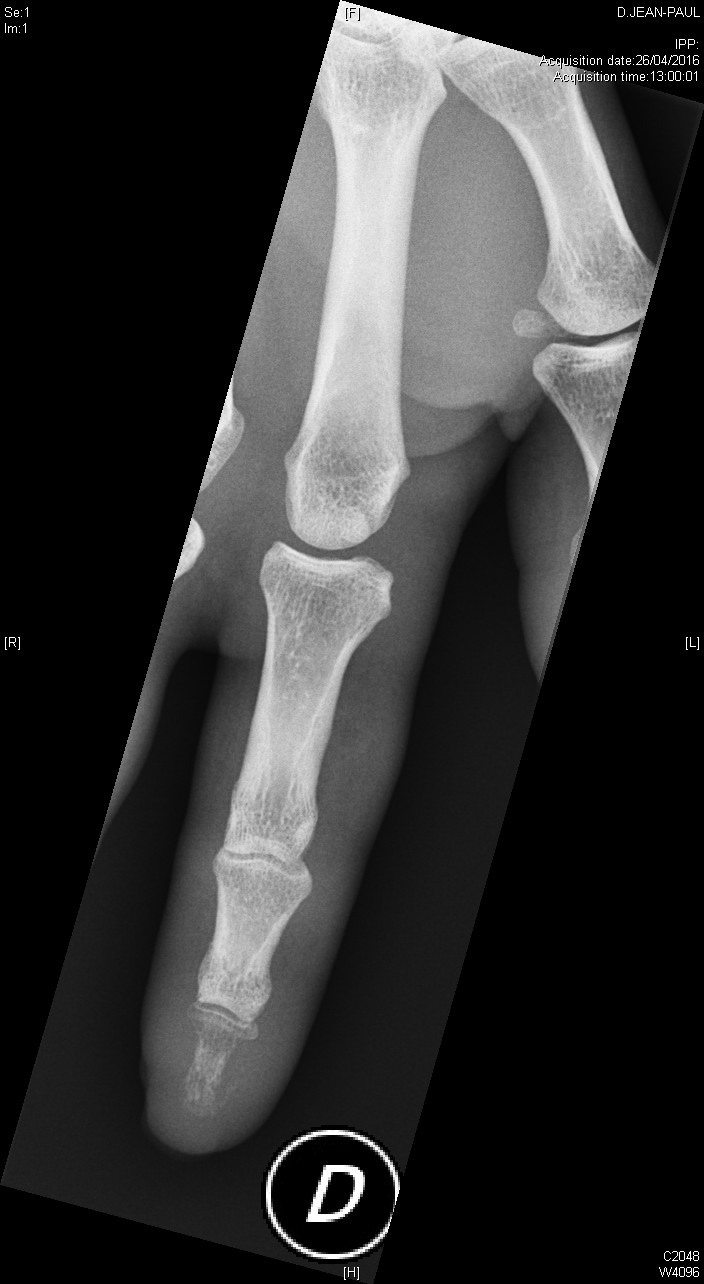

Ostéite de la phalangette

Polyarthrite rhumatoïde séropositive, sévèrement érosive aux pieds